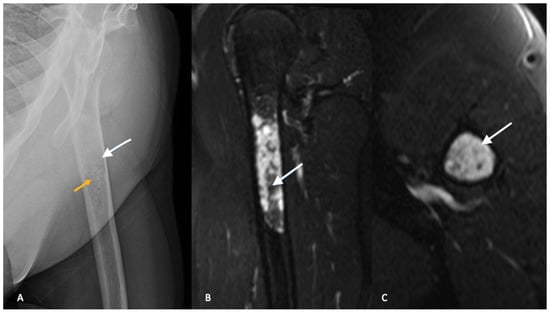

Plain radiographs with orthogonal views of the entire involved bone should be ordered as part of the initial workup. In conventional intramedullary chondrosarcoma, radiographs typically demonstrate mixed lesions with lytic and blastic activity [13]. Classically, the calcification pattern is described as “rings and arcs”, with the rings representing sclerosis and the arcs representing chondroid matrix. The distinction between ACTs and enchondroma is difficult and plain radiographs are not reliable in differentiating between the two entities [14,15]. Both ACTs and enchondromas tend to demonstrate a geographic lesion with lobular margins. Larger lesions (>5 cm) in the proximal metaphysis and endosteal scalloping favor a diagnosis of ACT [13,14] (Figure 1).

Similar to plain radiographs, differentiating between benign enchondromas and low-grade chondrosarcomas or ACTs is challenging with MRI. The findings of cortical thickening, intramedullary edema, bony expansion and entrapped fat are suggestive of an ACT but not diagnostic (Figure 1B,C) [19,20]. There continues to be significant interobserver variability and misdiagnosis with MRI as a diagnostic tool in the evaluation of ACTs and the diagnosis cannot be made on imaging alone [19].

Figure 1. Radiograph (A) of the left proximal humerus demonstrates subtle lucency with internal stippled calcified foci (yellow arrow), in keeping with chondroid matrix. Subtle endosteal scalloping is present (white arrows) without cortical breakthrough or periosteal reaction. Sagittal (B) and axial (C) T2-weighted images with fat saturation of the same patient demonstrating a lobulated T2 hyperintense mass. A few stippled areas of low signal intensity represent chondroid matrix (white arrow). The lesion measures greater than 5 cm in length. Axial images demonstrate endosteal scalloping at the anterolateral border. No periostitis or cortical breakthrough. Imaging features are in keeping with an atypical cartilaginous tumor, which was confirmed on pathology after surgical curettage.